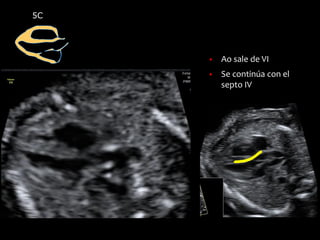

5C

▪ Ao sale de VI

▪ Se continúa con el

septo IV

▪ Se dirige hacia la

derecha, en medio de

la aurículas

▪ La válvula Ao abre y

cierra con normalidad,

dejándose de visualizar

en sístole

▪ Por Doppler color la

Ao no presenta

aceleraciones ni

reflujos